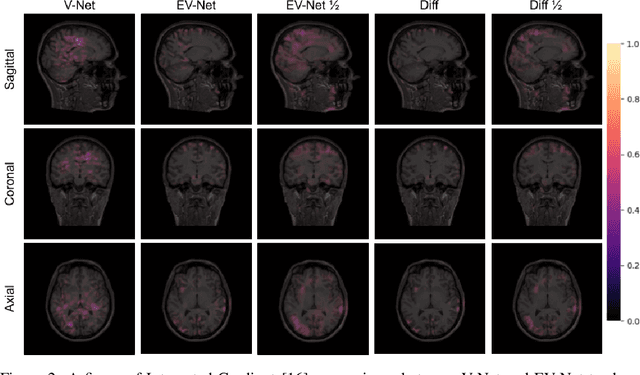

Abstract:Diffusion MRI (dMRI) is the only non-invasive technique sensitive to tissue micro-architecture, which can, in turn, be used to reconstruct tissue microstructure and white matter pathways. The accuracy of such tasks is hampered by the low signal-to-noise ratio in dMRI. Today, the noise is characterized mainly by visual inspection of residual maps and estimated standard deviation. However, it is hard to estimate the impact of noise on downstream tasks based only on such qualitative assessments. To address this issue, we introduce a novel metric, Noise Uncertainty Quantification (NUQ), for quantitative image quality analysis in the absence of a ground truth reference image. NUQ uses a recent Bayesian formulation of dMRI models to estimate the uncertainty of microstructural measures. Specifically, NUQ uses the maximum mean discrepancy metric to compute a pooled quality score by comparing samples drawn from the posterior distribution of the microstructure measures. We show that NUQ allows a fine-grained analysis of noise, capturing details that are visually imperceptible. We perform qualitative and quantitative comparisons on real datasets, showing that NUQ generates consistent scores across different denoisers and acquisitions. Lastly, by using NUQ on a cohort of schizophrenics and controls, we quantify the substantial impact of denoising on group differences.